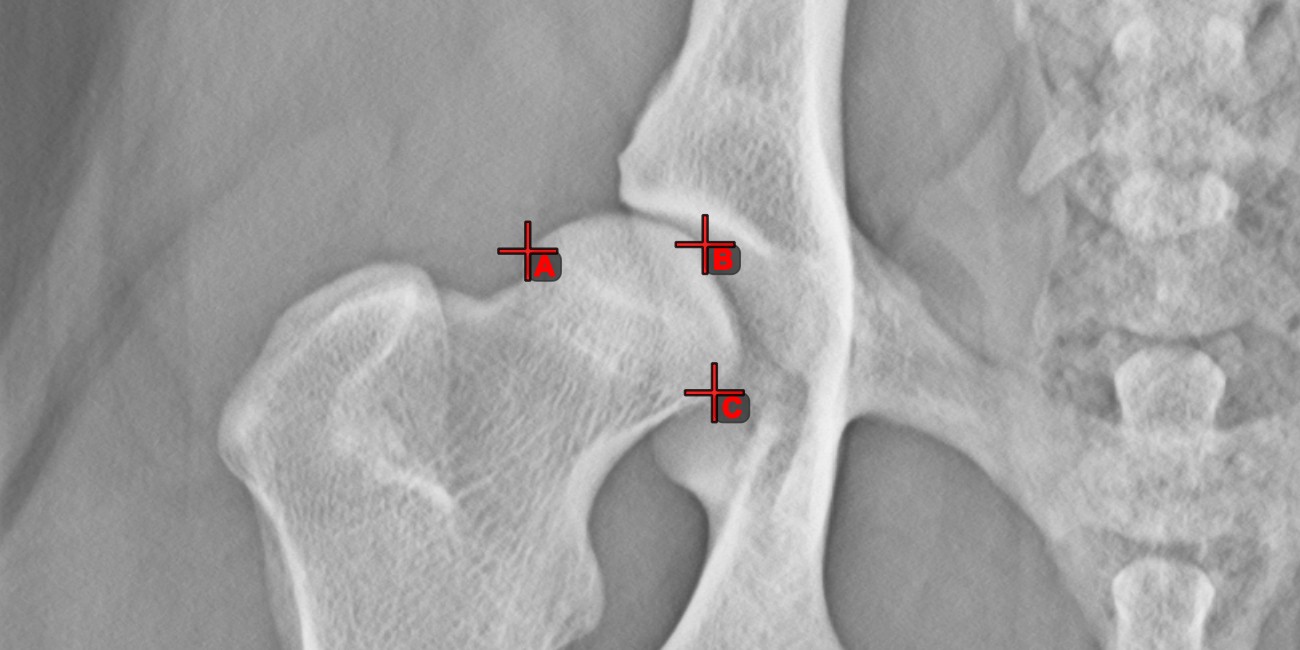

Measurement Point¶

Measurement Point

tool. Each point is assigned with a letter for better identification.Select/Move Item

tool. Select the point by using the assigned mouse button of the tool, and then move it freely anywhere on the image.